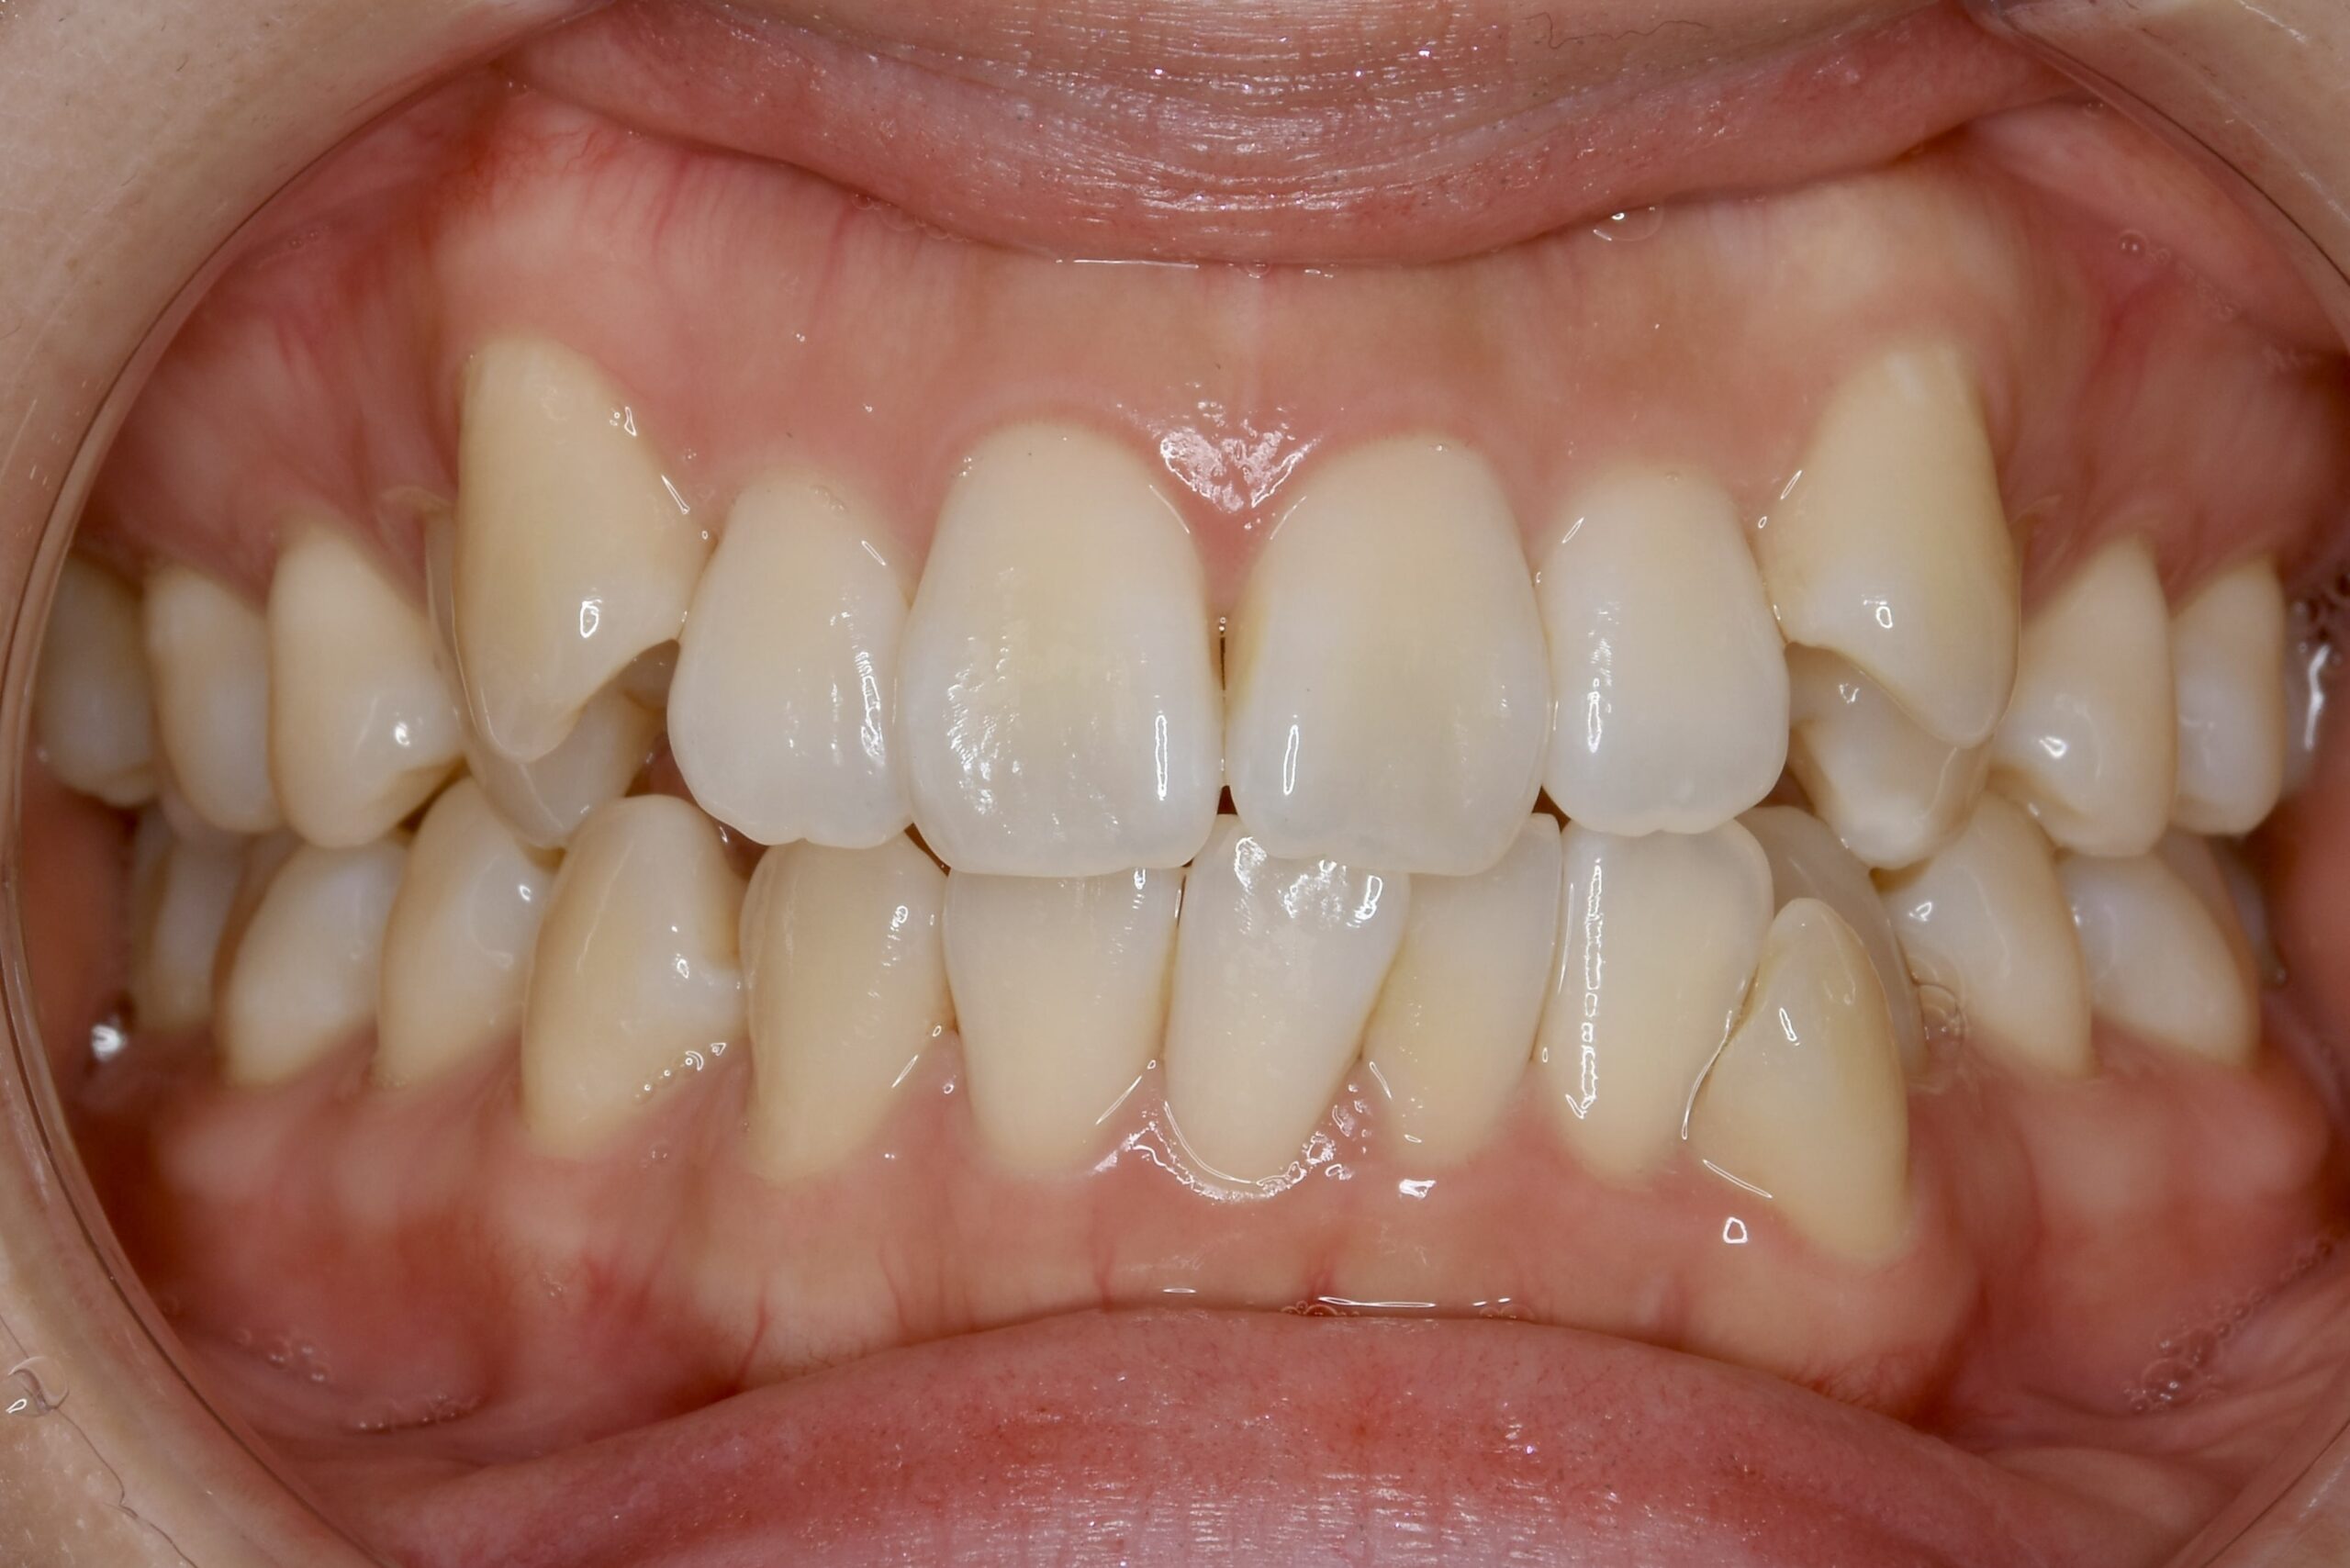

| 主訴 | 写真を見て歯並びが気になる。特に下の前歯はガタガタが強く治したい。 |

|---|---|

| 診断名・主な症状 | 叢生 |

| 年齢 | 19歳 |

| 治療内容 | 上下とも歯並びの幅を広げることでできたスペースを利用して、ガタガタを解消しました。 |

| 使用装置 | 表側矯正(ワイヤー) 矯正用ミニインプラント |

| 抜歯部位 | 抜歯なし |

| 治療期間 | 1年10ヶ月 |

| 通院回数 | 25回 |

| 費用 | 91万円程度(税別) 220 |

| リスク・副作用 | 痛み、歯肉退縮、歯根吸収、抜歯に伴う出血や腫れが生じることがあります。 |